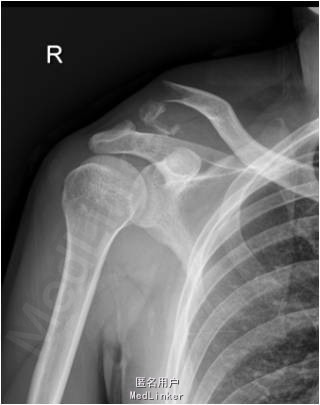

患者男,25岁,因“摔倒后右肩部疼痛伴活动障碍6小时”入院。患者6小时前不慎摔倒后右肩部疼痛伴活动障碍,急诊入院。

查体:右肩部肿胀,局部皮肤破损,无骨外露,无压痛,未引出骨摩擦音及骨摩擦感。左上肢及双下肢其余关节未见明显异常。 X线检查提示:右侧锁骨粉碎性骨折

诊断:右侧锁骨粉碎性骨折。目前拟行右肩关节镜检,关节镜监视下锁骨远端骨折双Endobutton复位内固定,必要时改锚钉复位内固定术。